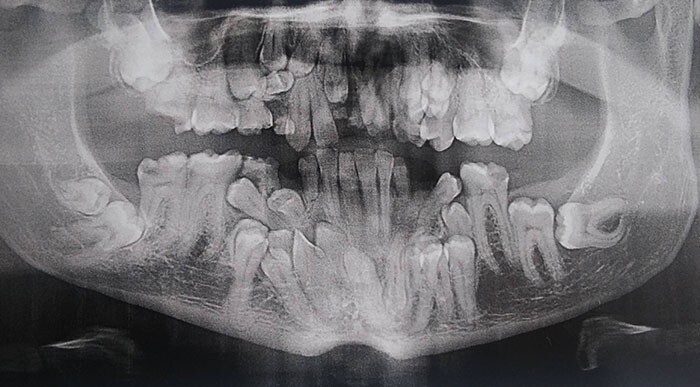

«Я дантист, но рентгеновские снимки детей 6-12 лет меня немного пугают до сих пор»